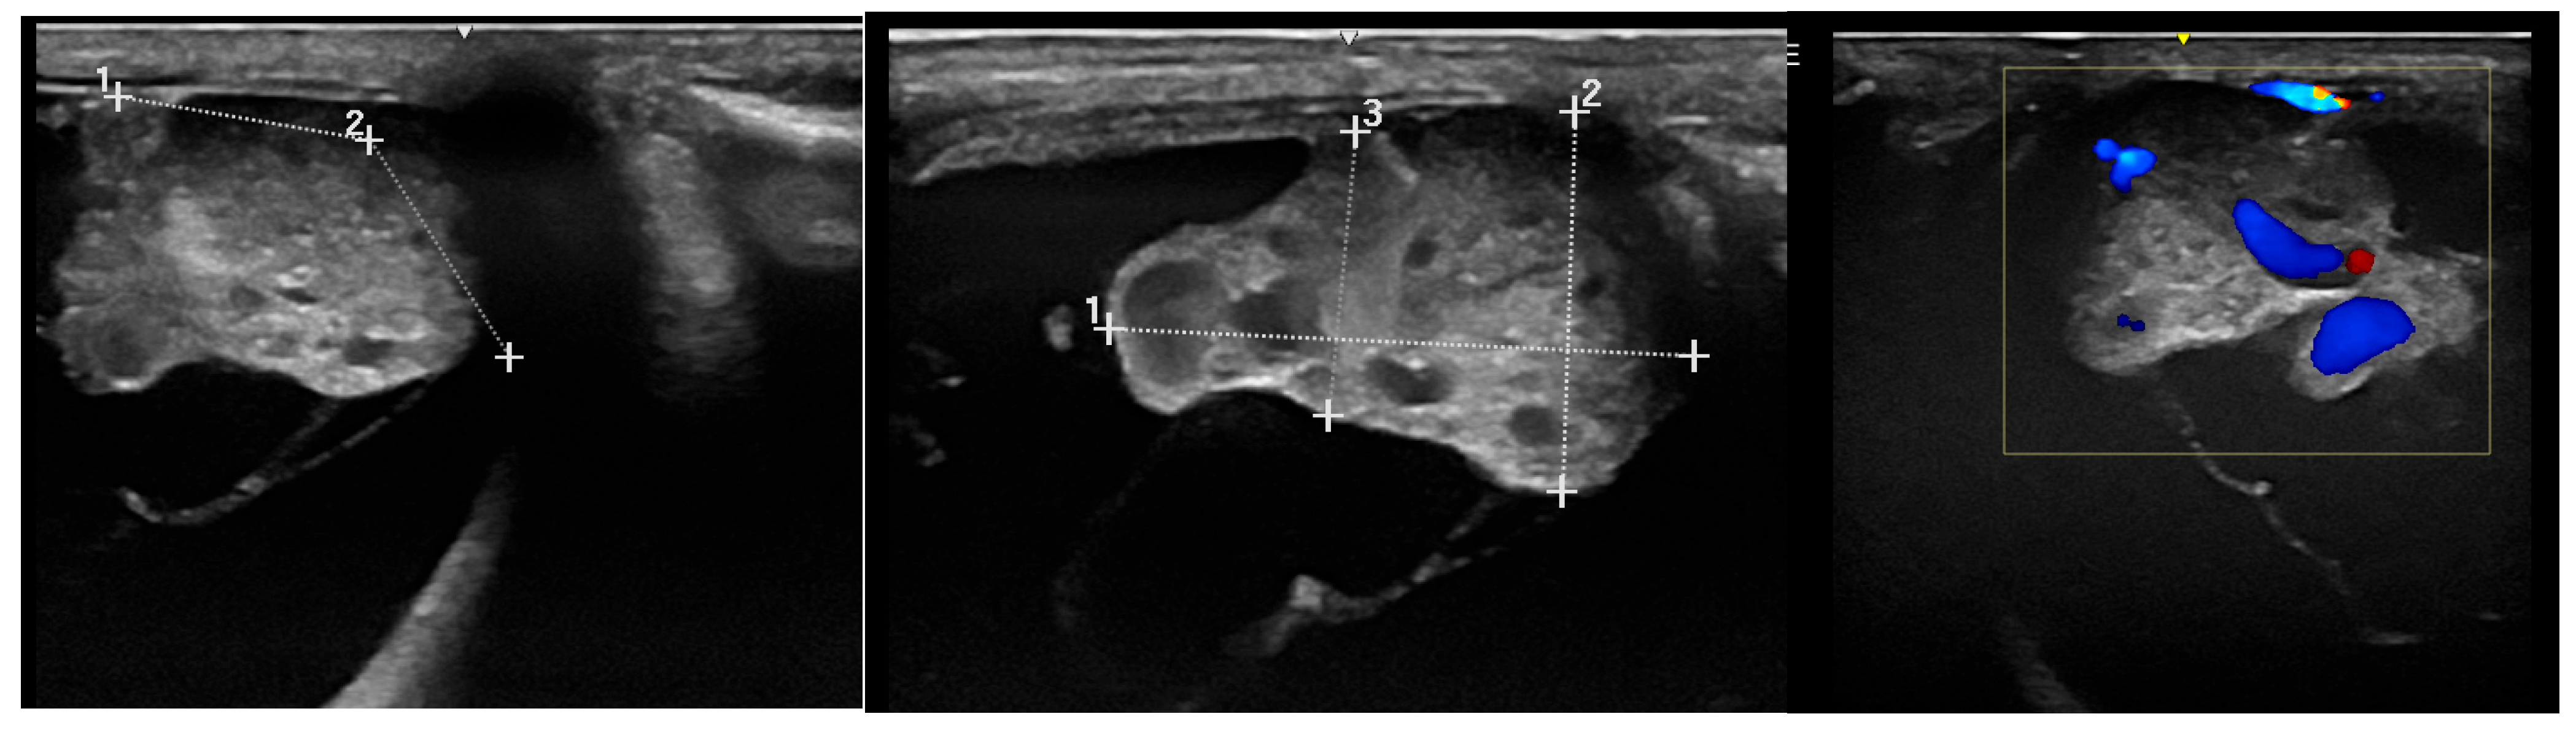

3.2.1. Ultrasonography

3.2.2. Sectional Imaging